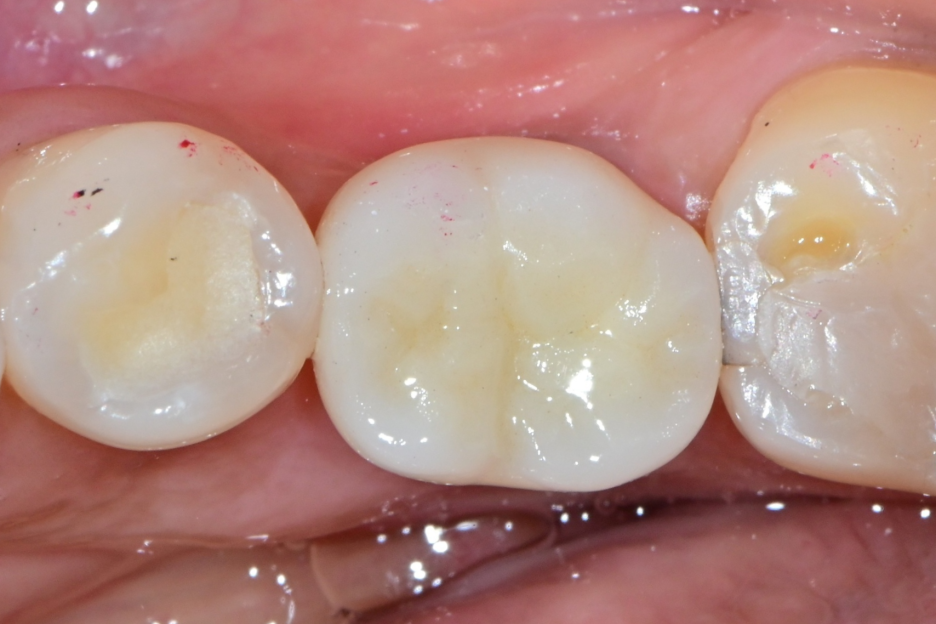

✔ 보철 문제일 경우 (가능)

| 보철물 교체 전 염증과 출혈이 있는 잇몸 | 보철물 교체 후 회복된 잇몸 |

✔ 음식물 끼임

✔ 보철 형태 문제

→ 보철 교체로 해결 가능